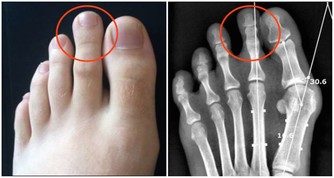

醫學專家發現,無論是左側卧還是右側卧,都有可能導致意外發生——睾丸扭轉。

睾丸“居住”在陰囊內,左右各通過一條叫做精索的組織與身體相連,

精索長有為睾丸提供血液循環的血管,男性在採用側卧睡姿睡覺時,

睾丸和陰莖被擠壓在兩腿之間,所承受的壓力比站立時要明顯得多。

部分男性、尤其是青少年睡覺時動來動去,雙腿也扭來扭去,

有可能把精索也“扭”成了一團,出現扭轉和“打結”的情況。

由於給睾丸供應營養和排出代謝物的血管從精索中通過,

一旦精索發生扭轉,睾丸就得不到營養,代謝物也不能排出,

若扭轉時間超過12個小時,睾丸就有可能缺血、壞死。